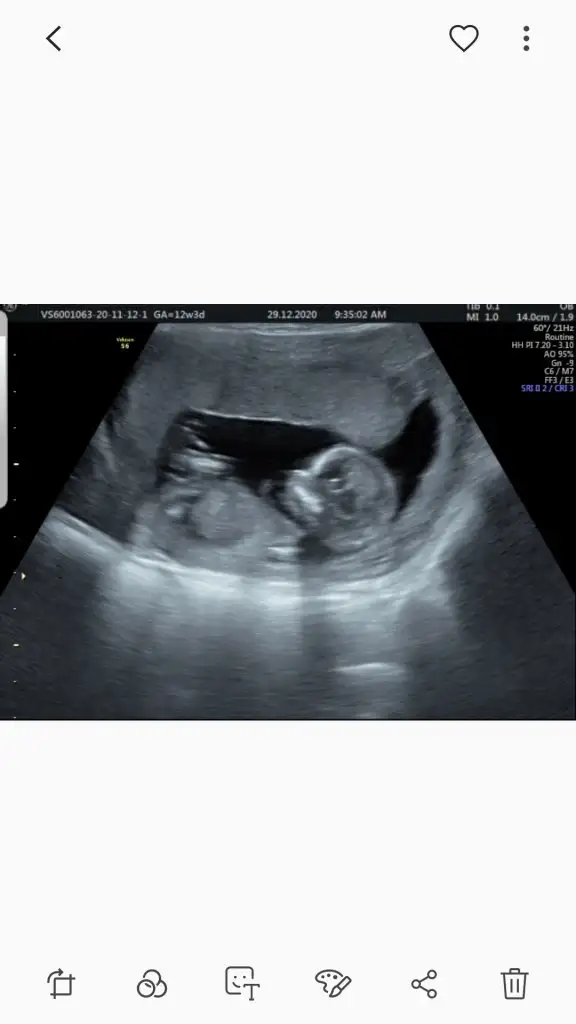

Geçen hafta da bakmıştık doktor da sen de kıza benziyor demiştin Ikra meyra :) Ama bugün doktor erkeğe benziyor dedi tam belli olmuyor nubu tek ultrason fotoğrafı var bugünden ama bir denemek istedim bakalım bugün ne diceksin :)

Ölçümün hemen yanında nubu yüksek görünüyor 12+5 gore erkek görünüyor